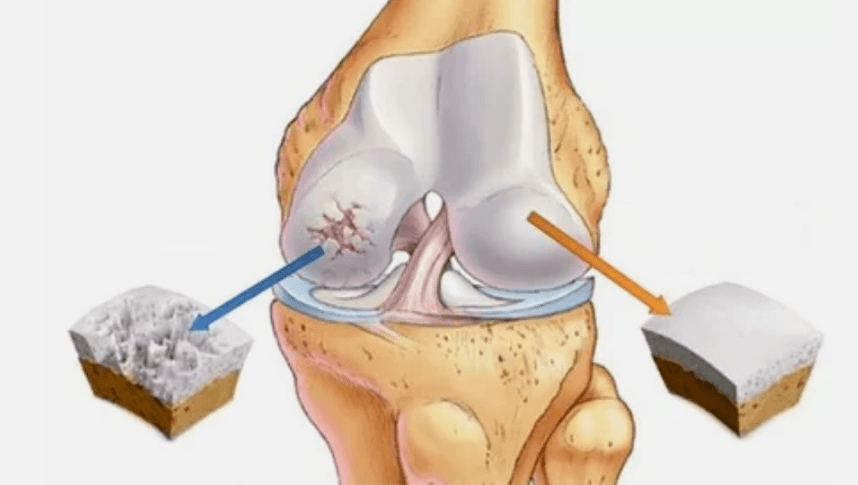

Eklemin artrozu uzun süre gelişir, başlangıçta sadece hiyalin kıkırdağını etkiler, daha sonra kemiklere yayılır, sinovyal kabuğu, kasları ve tüm eklem kapsülünü içerir. Artrozun ilk veya erken aşamasında, lezyon biraz ortaya çıkar: sıkı çalışma, şişlik, cildin kızarıklığından sonra küçük ağrılar. Rahatsız edici duyumları görmezden gelme nedeniyle, eklem deforme olur, iltihaplanır, şiddetli ağrı getirir, sabahları zirve düşer. Hastalık, eklemin gelişiminden sonra ağrının ortadan kaybolması ile karakterizedir. Tedavi edilmezse, bir kişi eklemin hareketliliğini tamamen kaybeder.

- Hiyalin kaplama patolojileri. Kıkırdağın incelmesi, patolojik dokularının - kemik yapılarının değiştirilmesine yol açar.

- Anormal büyümeler kıkırdak - osteofitlerde görülür.

- Resimde fark edilebilir hale gelen eklem boşluğundaki boşluğu azaltmak. İhlalin aşaması teşhis-tantenolog tarafından belirlenir. Hasta uzuvu tamamen düzeltin ve bükememeyi hisseder;